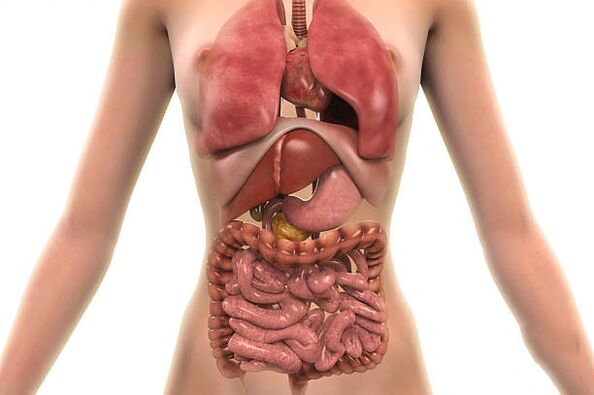

البكتيريا الطفيلية في جسم الإنسان، في أي أعضاء يمكن أن تعيش؟

توجد في جسم الإنسان وعلى جلده بكتيريا بسيطة؛ يمكن أن تكون أحادية الخلية أو متعددة الخلايا.

تسمى الطفيليات التي تعيش على الجسم بالطفيليات الخارجية. يشمل هذا النوع البق والقمل ومسببات أمراض الجرب المماثلة. ويطلق على البعض الآخر اسم الطفيليات الداخلية لأنها تعيش داخل جسم الإنسان. وتشمل هذه الأميبا والديدان ويرقات الحشرات.

ولكل من الطفيليات مكانه المثالي في جسم الإنسان، حيث تتوفر لديه كافة الظروف اللازمة لنمط حياة طفيلي، أي العناصر الغذائية الضرورية للنمو والتكاثر. يمكن لبعضهم التحرك أثناء نموهم.

في أغلب الأحيان، يمكن العثور على الطفيليات الداخلية في الأمعاء والعضلات والدم والرئتين والقلب والكبد. حتى أن بعض الأنواع تعيش في الأنسجة العصبية. تعيش الطفيليات خارج الرحم على الجلد.